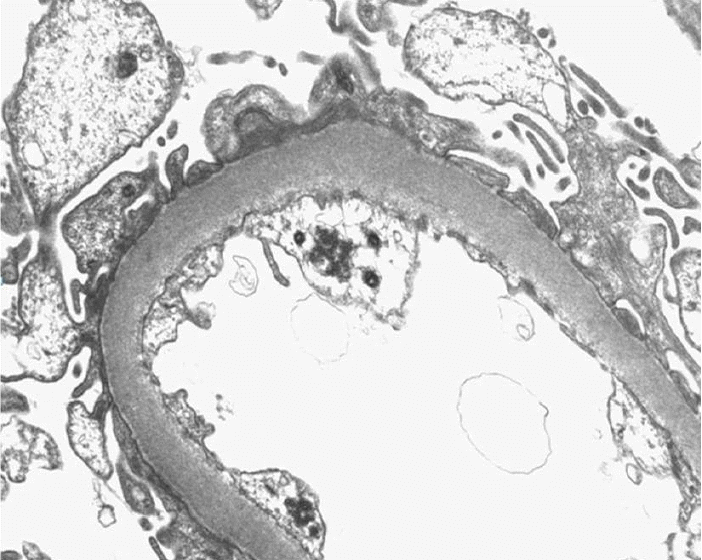

신장 조직 검사 소견: 광학 현미경에서 29개의 사구체가 관찰되었으며, 1개는 전반적으로 경화되었고, 6개는 국소적 경화 소견을 보였다. 간질은 경미하게 증식되어 있고 모세혈관 안에 백혈구가 침윤되어 있었고, 핵의 파편들도 관찰되었다. 사구체 기저막은 비후되어 있지 않았고 신세뇨관과 사이질, 혈관에는 특이소견이 없었다. 면역형광염색에서도 IgA나 C3 침착은 없었다. 전자현미경 검사에서는 경미한 간질 증식이 있으나 전자 밀도 침윤 소견은 거의 없었고 내피세포의 세포질에 세관망상 봉입체가 관찰되었다(Figs. 1 and 2).

Figure 2.

Electron microscopy showing tubuloreticular inclusion bodies in endothelial cells (× 12,000).